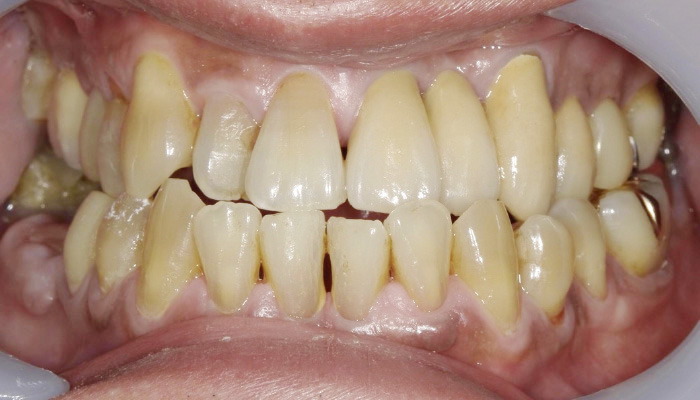

症例 22

治療前

治療後

| 主訴 | 歯の違和感。 |

| 先生からの提案 (治療内容について) |

歯の違和感があるとのことで来院。 古いプラスチックや被せものが装着されていたのと、歯間離開があり、見た目もあまりよくなかったので、仮歯で患者さんと形などを話合い決定し、最終補綴物へ移行した。 |

| 治療期間 | 2か月 |

| 治療費 | 650,000円 |

| 治療のリスク | 歯ぎしりが強いので歯根破折する可能性がある。 |